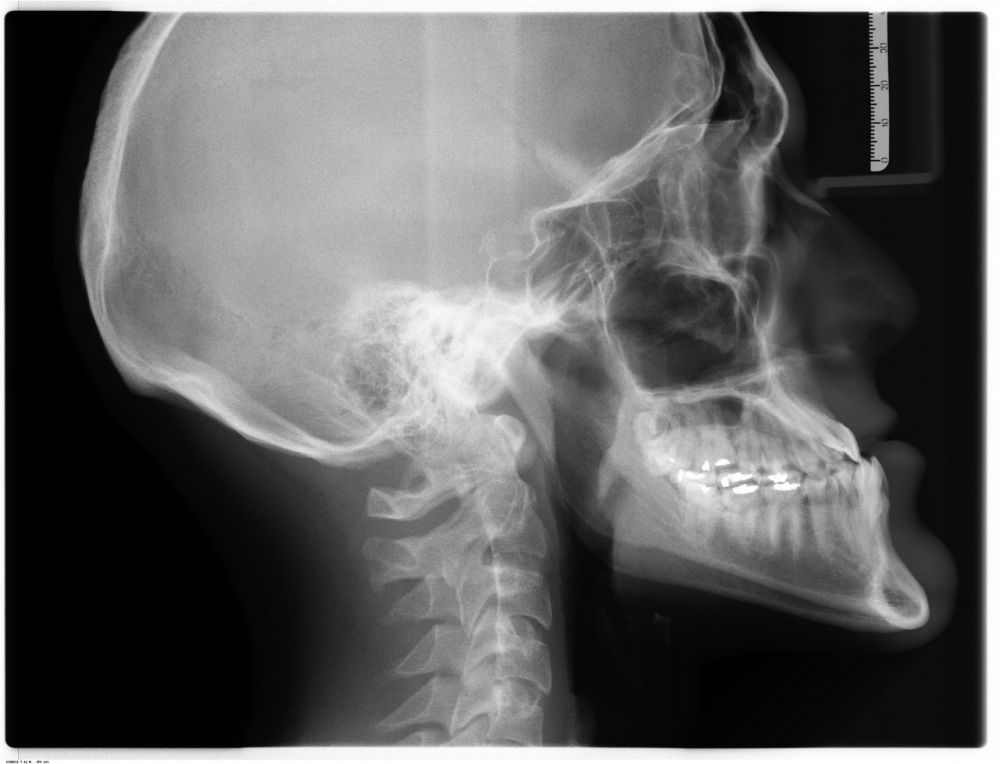

Røntgenundersøgelse: En komponent i moderne diagnostik